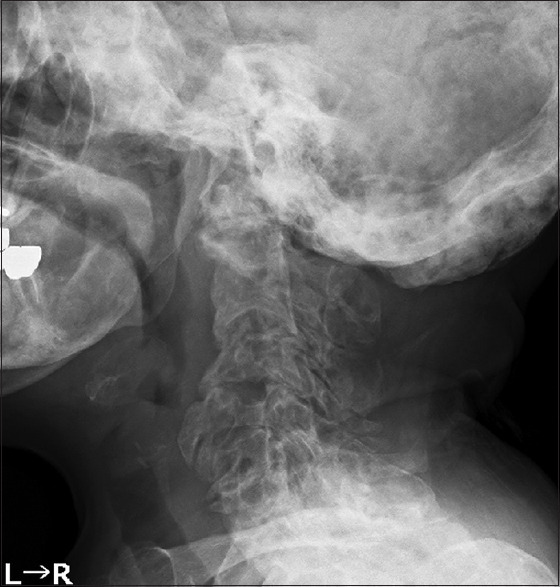

纤维发育不良(FD)是一种罕见的骨骼疾病,其特点是正常骨骼被纤维结缔组织取代,导致骨骼形成异常。本病例报告详细介绍了一名颅椎骨交界处纤维发育不良的 61 岁女性患者的成功治疗过程。该患者曾有颅内脑膜瘤病史,并已被诊断为 FD,在一次跌倒后出现步态障碍和肌肉无力。影像学检查显示,患者的颅骨和颈椎有广泛的多发性 FD 病变,C2 骨突骨折导致脊髓受压。患者接受了枕颈固定和减压手术。术中使用了 O 型臂导航,以确保准确放置螺钉和有效减压。该手术可以正确定位C2和C3椎弓根螺钉、切除增生的枕骨和C1后弓、放置枕骨钢板并避开囊肿组件。在两年的随访中,没有发现螺钉松动的迹象,患者的临床症状明显改善。该病例强调了量身定制的手术策略和先进导航技术在处理复杂 FD 病例,尤其是涉及 CVJ 的病例中的重要性。它还凸显了治疗多发性 FD 所面临的挑战,因为完全切除往往是不可行的。该病例的成功结果支持使用减压手术结合稳定术来缓解症状并预防进一步的并发症。

Fibrous dysplasia (FD) is a rare skeletal disorder characterized by the replacement of normal bone with fibrous connective tissue, leading to abnormal bone formation. This case report details the successful treatment of a 61-year-old woman with FD at the craniovertebral junction (CVJ). The patient, who had a history of intracranial meningioma and had already been diagnosed with FD, experienced worsening gait disturbance and muscle weakness following a fall. Imaging studies revealed extensive polyostotic FD lesions in the skull and cervical spine, along with a C2 odontoid fracture causing spinal cord compression. The patient underwent occipitocervical fixation and decompression surgery. Intraoperative O-arm navigation was used to ensure accurate screw placement and effective decompression. This procedure allowed for proper positioning of the C2 and C3 pedicle screws, resection of the hyperplastic occipital bone and C1 posterior arch, and placement of the occipital plate with avoiding the cyst components. At a 2-year follow-up, there were no signs of screw loosening, and the patient showed marked clinical improvement. This case emphasizes the importance of tailored surgical strategies and the use of advanced navigational technologies in managing complex FD cases, particularly those involving the CVJ. It also highlights the challenges of treating polyostotic FD, where complete resection is often unfeasible. The successful outcome in this case supports the use of decompressive surgery combined with stabilization to relieve symptoms and prevent further complications.